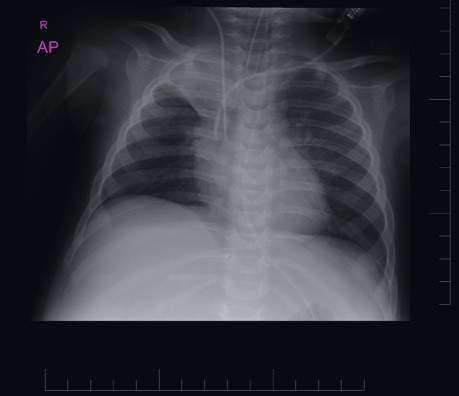

60 Akútne respiračné zlyhanie

MUDr. Ivana Gondová, PhD.